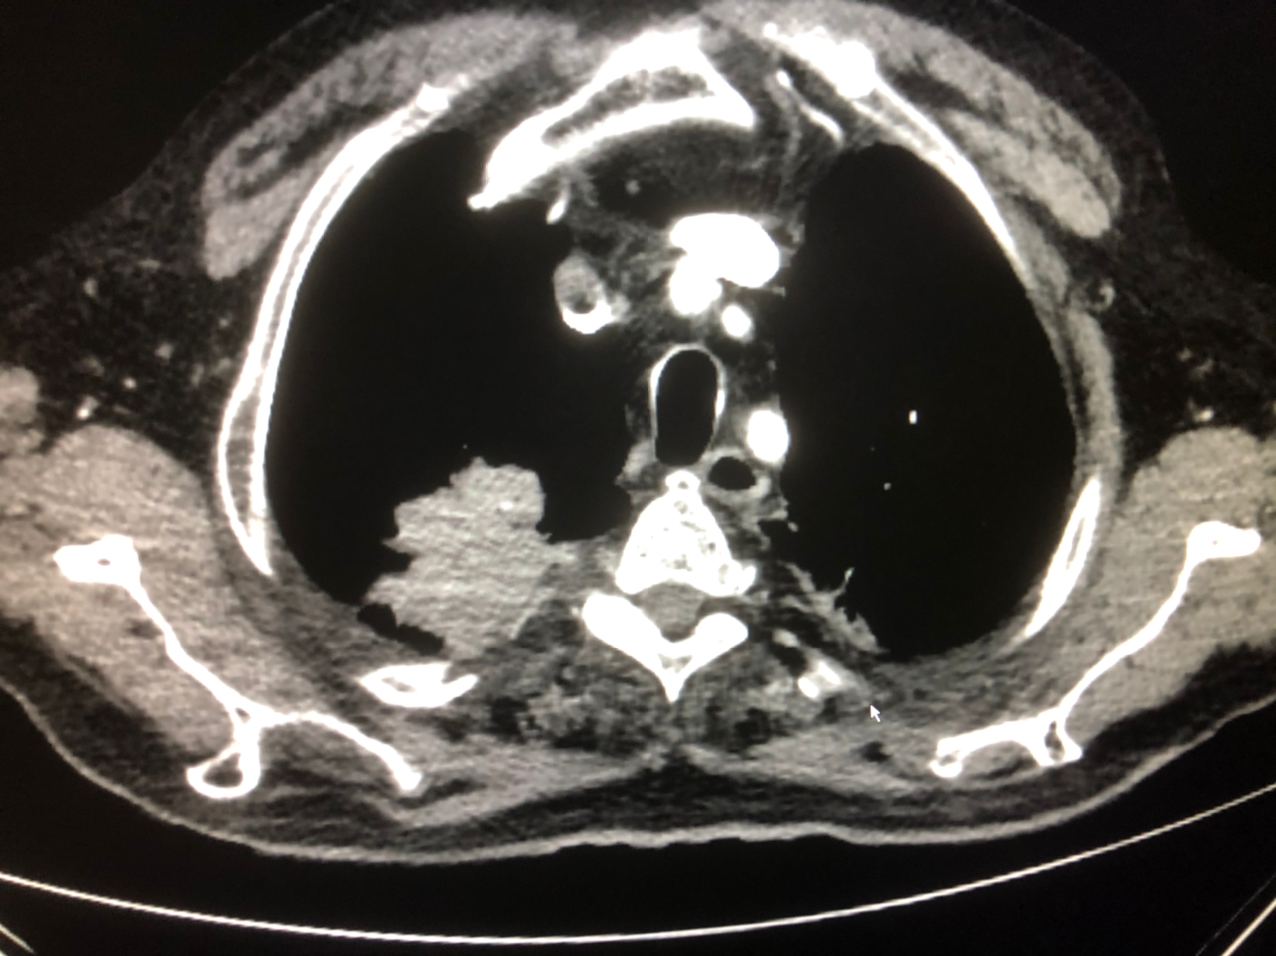

Можно покрутить? «накиньте» срезов, плиз

Ср или Панкост? Ребро целое? Гидроторакс?

Панкост. Ребро целое, но инфильтрация в спинной канал, отсюда корешковая симптоматика

Покажите плиз

Покрутить бы

Случай классный

Я не могу столько фот телефоном делать, чтоб крутить, а скриншот у нас заблокирован